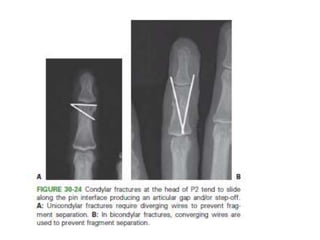

• Condylar fractures

– CRIF- converging or diverging.

• #88  Figure 30-58 Transverse P1 fractures without comminution should achieve sufficient interfragmentary stability to have axial rotational control with a single wire alone that targets the (A) intercondylar notch and going (B) all the way to the subchondral bone.